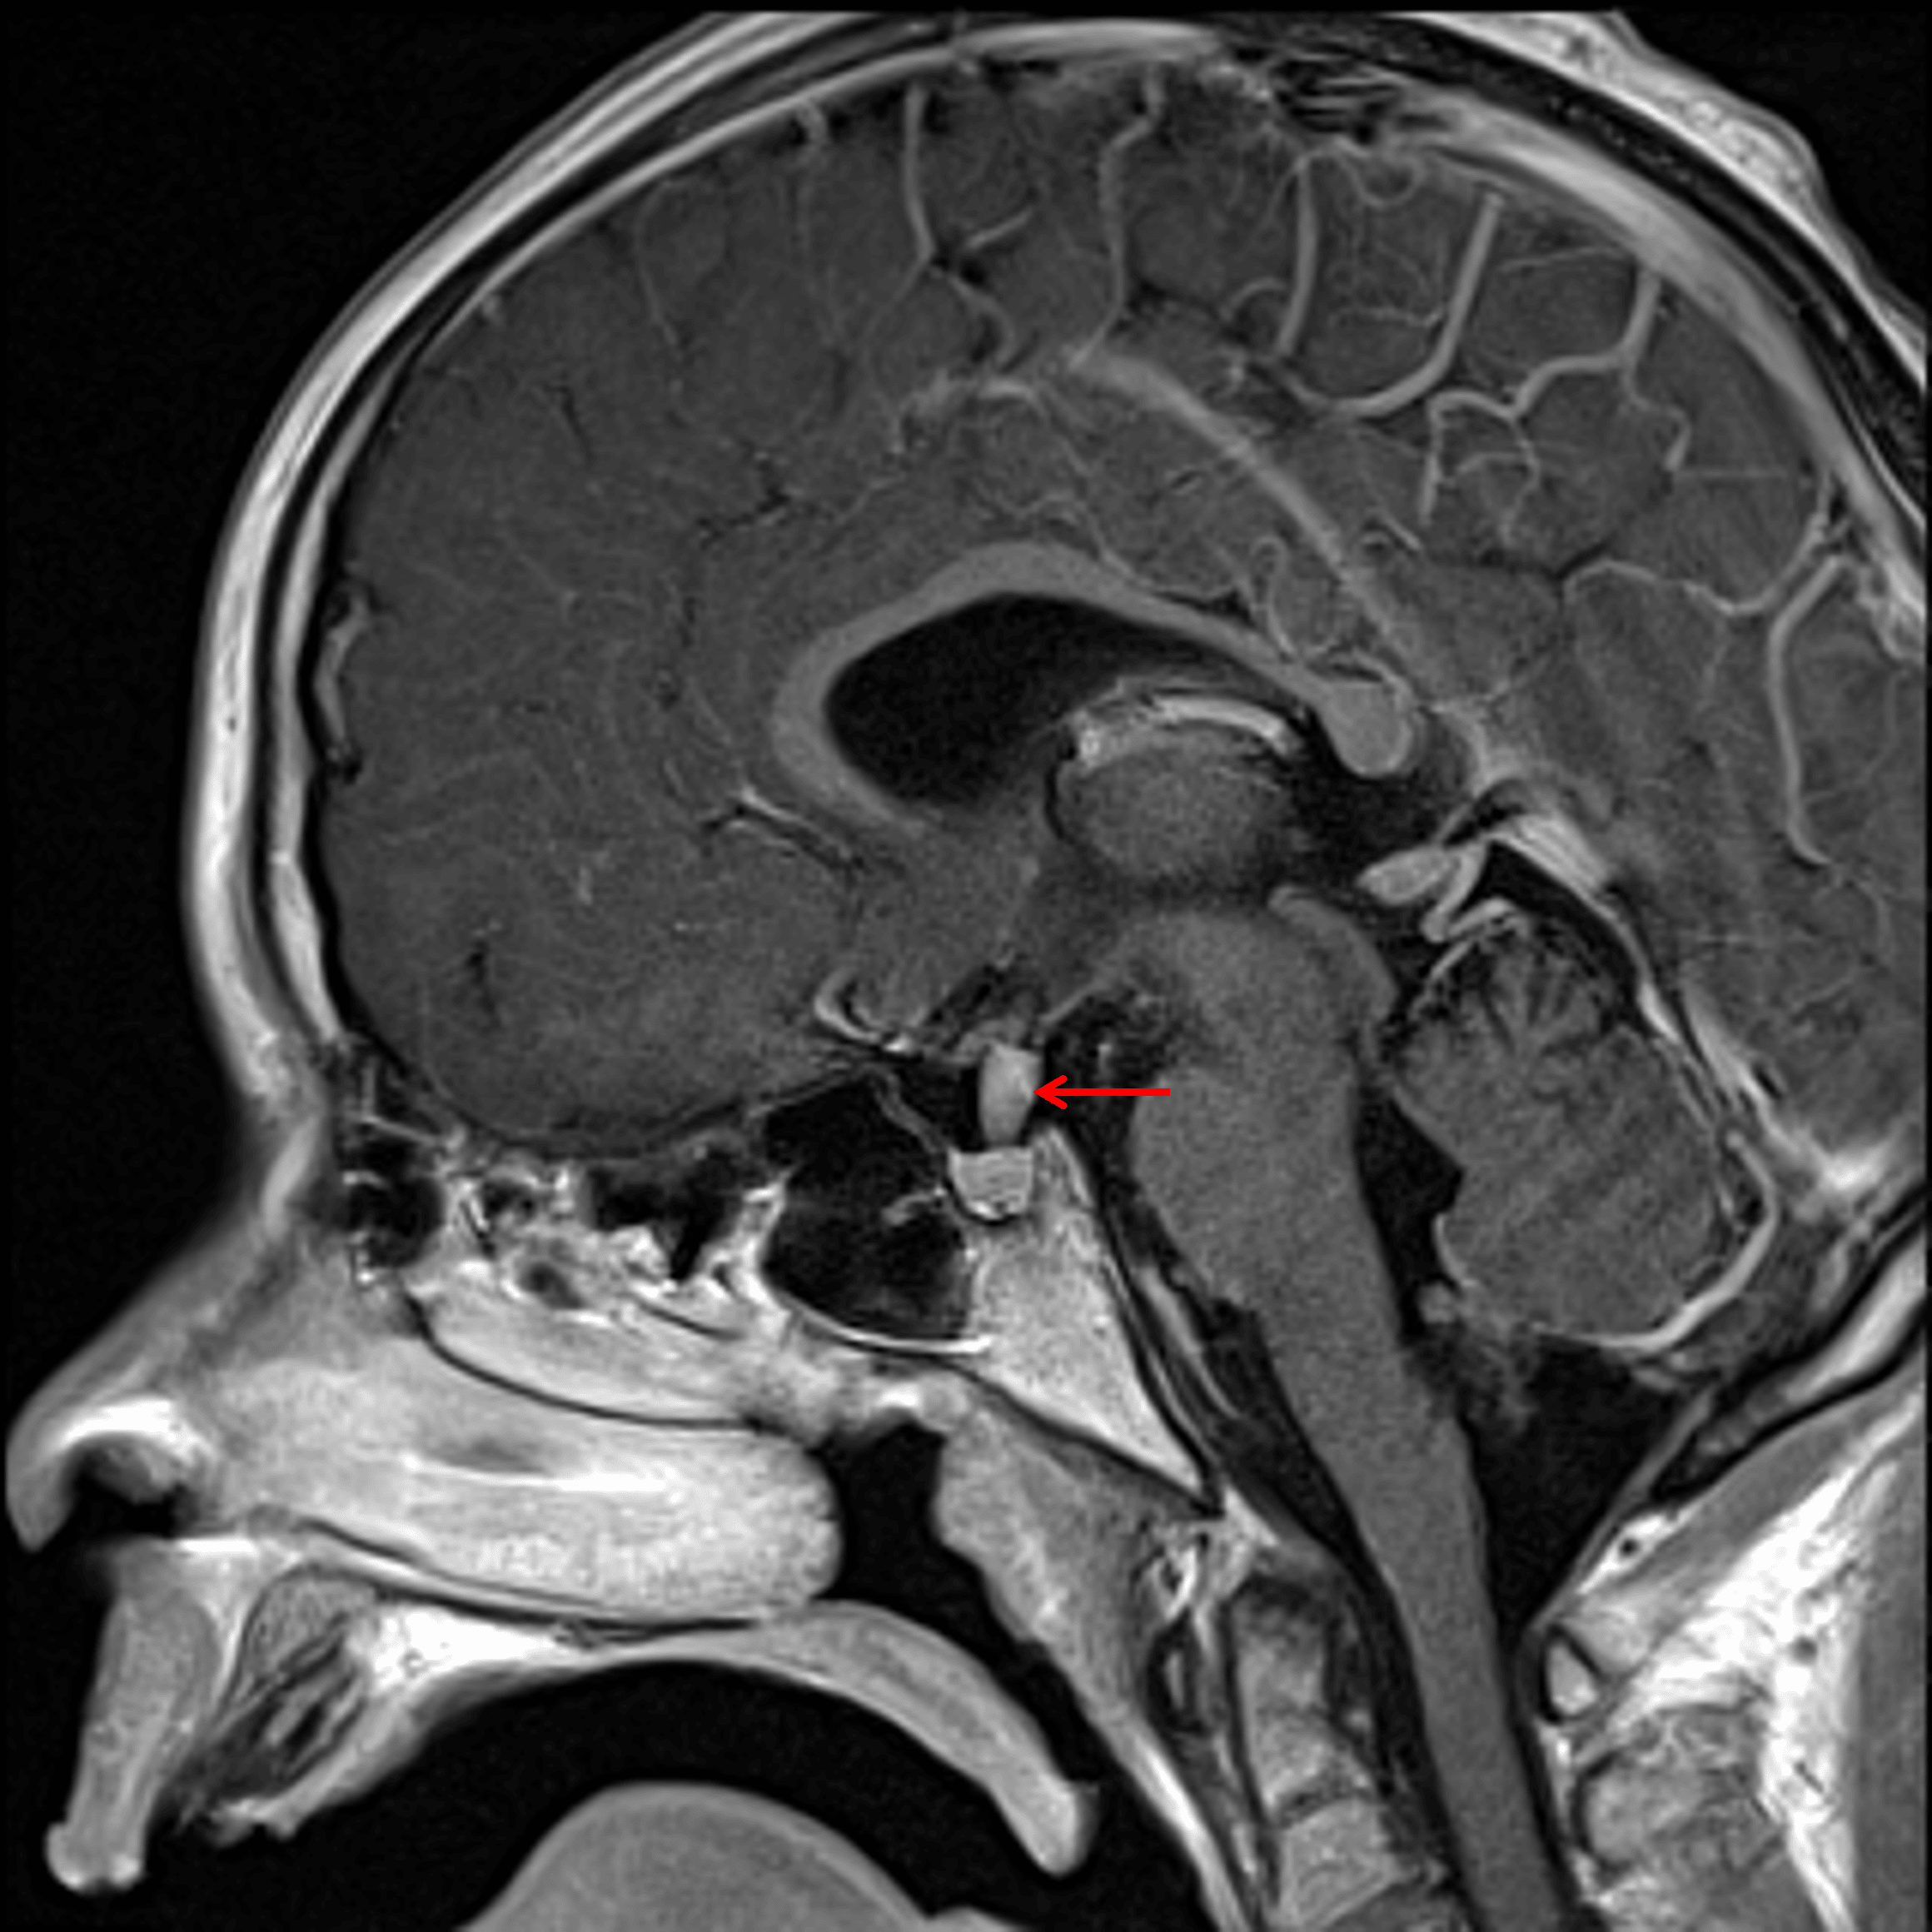

Diffuse enhancement of the pituitary stalk lesion (red arrow).